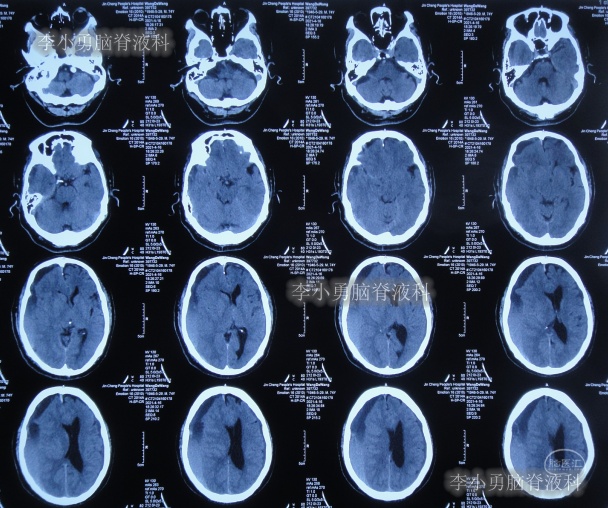

2021年4月16日(腰大池腹腔分流术后19天),因意识变差,查头部CT(图-4)后,急诊进行了硬膜下血肿引流术,并升高分流泵的压力200。

图-4:2021年4月16日头部CT